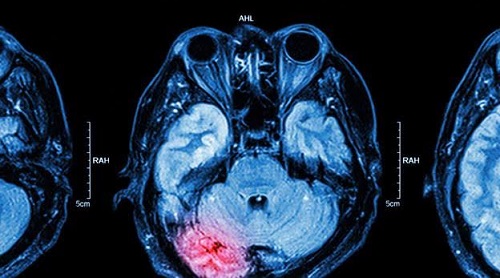

March 2, 2016, by Brooke Chaplan – The brain is one of the body’s most vital organs and just like other parts of our bodies, the brain is prone to disease and illness. Mental health deals not only with emotions but also the physical brain. Today, advances in mental health research are making conditions like depression, PTSD, and psychiatric disorders easier to treat.

Researchers are closely inspecting how the brain develops during childhood to better understand how mental conditions can be treated and diagnosed. One breakthrough is the clue that young children with depression develop brains that differ in structure than those without. This research may hold the key to effectively treating and preventing many neurological conditions. Conditions like PTSD are now being looked at to see if childhood brings any precursors that could show if certain people are more susceptible or even genetically disposed to these kinds of mental illnesses.

The difficulty in treating PTSD is that it can manifest in various ways and with differing symptoms for different individuals. The criteria for diagnosing PTSD increases as more information is discovered about this condition. Electric patches designed to deliver charge to certain areas of the brain have already shown promising preliminary results in minimizing the symptoms of PTSD.